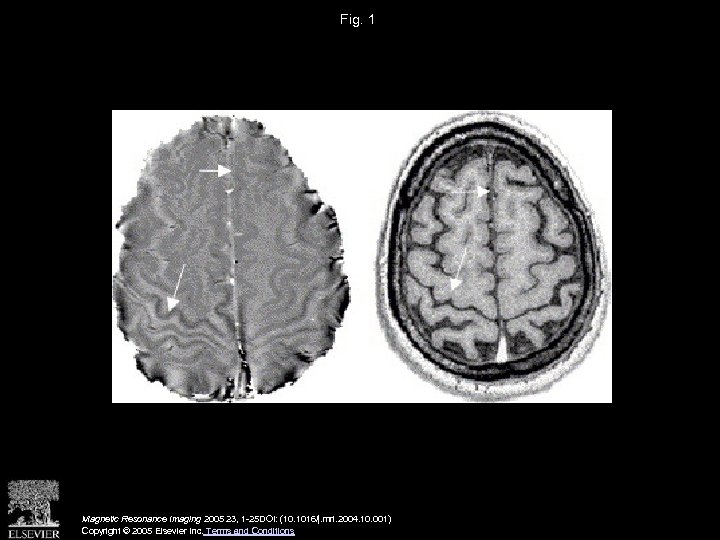

Fig. 1 Magnetic Resonance Imaging 2005 23, 1 -25 DOI: (10. 1016/j. mri. 2004. 10. 001) Copyright © 2005 Elsevier Inc. Terms and Conditions